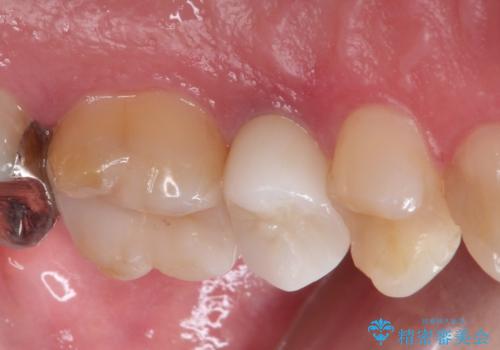

- 左上の後ろから3番目の歯のかぶせ物が適合不良であったので、根管治療を行い、オールセラミックを装着する計画としました。

またその隣の目立つ銀歯も同時に、セラミックに交換することとしました。

根管治療からかぶせ物まで精度の高い治療をおこないました。